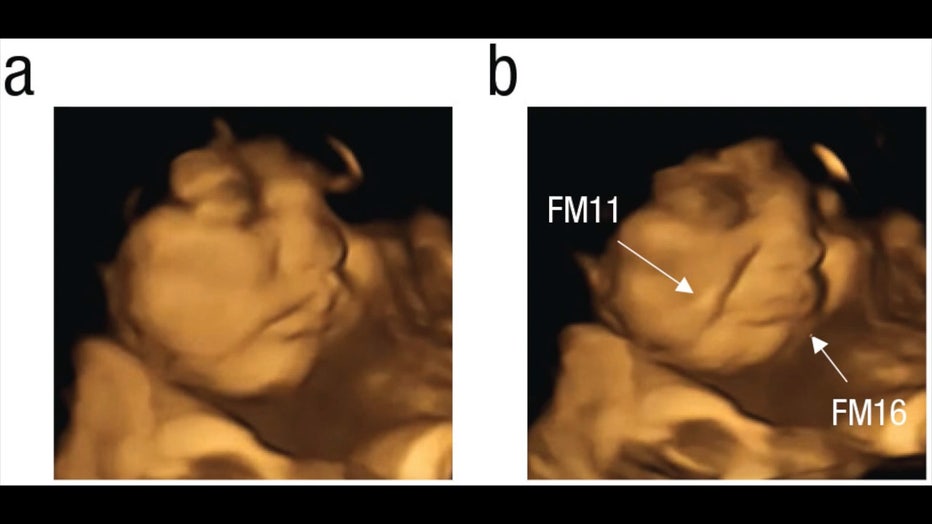

Fetus-carrot.jpg

Before and after image showing a fetus after its mother ingests a carrot capsule. (Beyza Ustun, Nadja Reissland, Judith Covey, Benoist Schaal, and Jacqueline Blissett via Storyful)

After a pregnant woman ingested either the kale or carrot capsule, it took about 30 minutes to see results, according to Blissett.

Each participant in the study would wait about 20 minutes after swallowing a capsule before they were given an ultrasound.

The fetuses exposed to the carrot capsule showed a more "laughter-face" expression, and the ones exposed to the kale capsules showed a more "crying-face" expression, according to researchers.